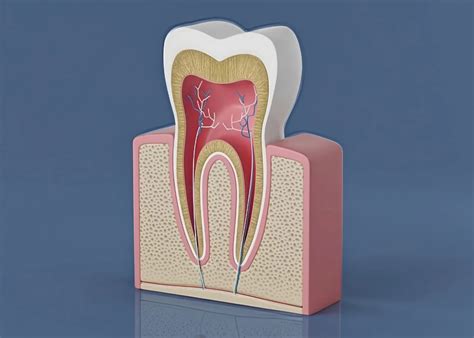

A root canal is essentially a deep cleaning of the internal structure of your tooth. When decay or trauma reaches the nerve (the pulp), it becomes inflamed or infected. If left untreated, this can lead to an abscess, severe pain, and potential bone loss in the jaw. The procedure involves removing the damaged pulp, disinfecting the internal canals, and filling them with a biocompatible material called gutta-percha.

• diagram of a root canal